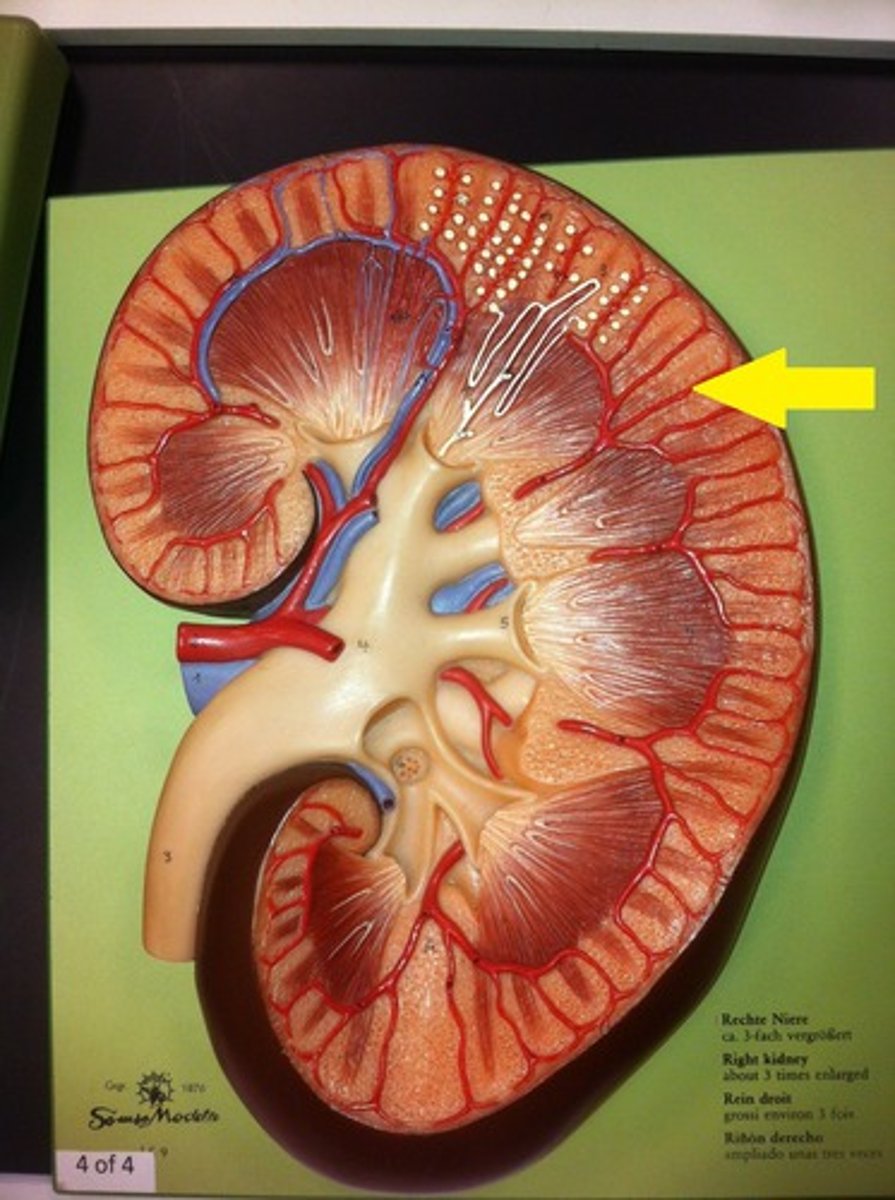

kidney

fibrous capsule

outer covering

renal cortex

renal medulla

renal papilla

major calyx

minor calyx

renal pelvis

renal pyramids

ureter

renal columns

renal artery

renal vein